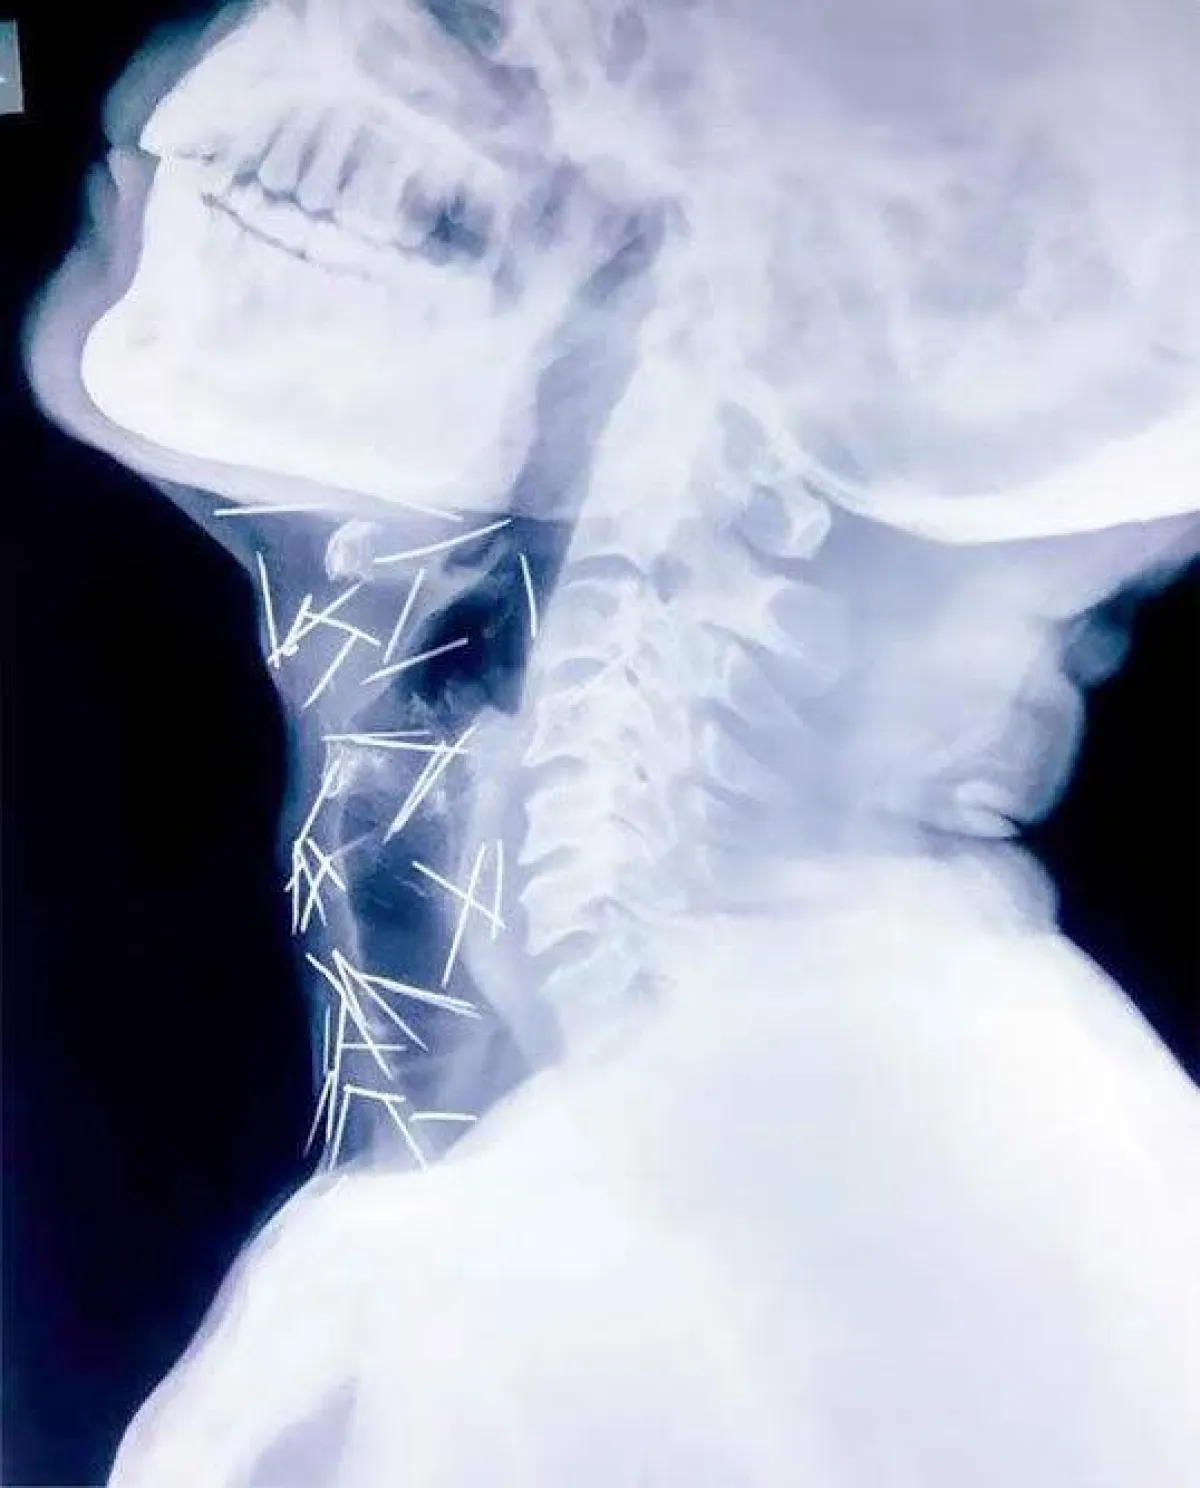

ويرقد الرجل حالياً في مستشفى "مومباي" استعداداً لإجراء الجراحة، التي سيتم خلالها ازالة 40 مسمار من الحلق و 25 من ساقه اليمنى و10 من أماكن متفرقة باليدين وباقي الجسد .

وقال إبنه "راجندرا": "اعتقدنا أن الأمر بسيط، ولكن شعرنا بالخوف بعد رؤية صور الاشعة ونحن لا نعرف كيف دخلت تلك المسامير، ووالدي نفسه لا يتذكر كيف حصل ذلك، وأكد الأطباء أن تلك المسامير لم تؤثر على وظائف حيوية في جسده".